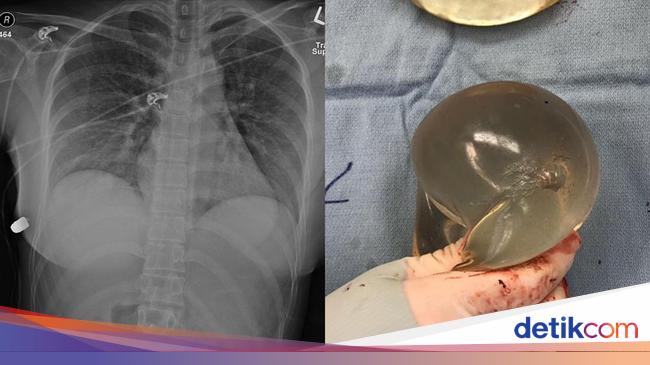

Viral kisah seorang wanita selamat dari tembakan misterius. Peluru tersebut menyangkut di implan payudara silkon miliknya, sehingga tidak sampai memicu cedera serius.

Tembakan itu tepat mengenai bagian atas putingnya. Beruntungnya, peluru tidak menembus organ vitalnya, melainkan tertahan di payudara implan berukuran 450 ml.

Setelahnya, wanita itu dipindahkan ke pusat trauma untuk menjalani operasi. Dokter harus mengangkat implan kedua payudaranya. Dokter menemukan saluran peluru tepat di bawah luka masuk hingga payudara kanan.

"Berdasarkan lintasan peluru masuk secara klinis dan evaluasi radiologis, satu-satunya sumber defleksi peluru dari peluru adalah implan payudara kiri. Implan ini melapisi jantung dan rongga intratoraks dan karena itu kemungkinan besar menyelamatkan nyawa wanita tersebut," tulis laporan tersebut yang dikutip dari People.